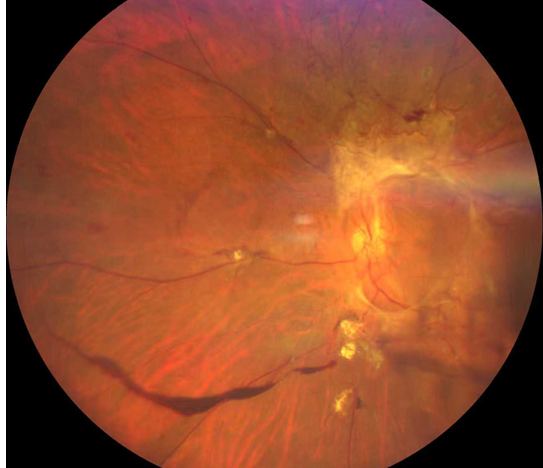

廈門眼科中心的檢查結(jié)果讓全家倒吸一口涼氣:

右眼視力0.05,左眼僅余眼前光感;

雙眼被確診為Ⅱ期增殖性糖尿病視網(wǎng)膜病變(以下簡稱“糖網(wǎng)”),并伴有黃斑水腫。

糖尿病視網(wǎng)膜病變

這意味著,如果再晚來幾天,視網(wǎng)膜損傷將不可逆轉(zhuǎn),他將永遠(yuǎn)失去光明。